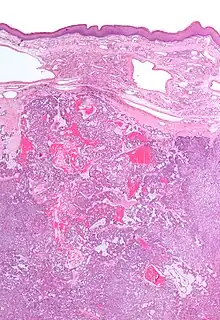

| Low magnification micrograph of a polymorphous low-grade adenocarcinoma, showing the typical variation of architectural arrangement. H&E stain. | |

- It has a varied microscopic architectural appearance, i.e. it is polymorphous.

PLGAs consist of a monomorphous cell population that has a varied histologic morphology.